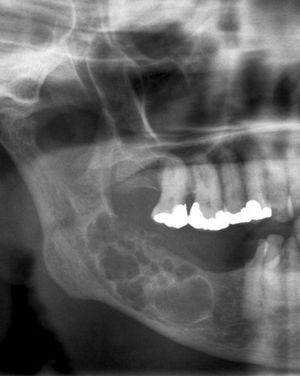

Diagnosis ??

Hint: soap bubble appearance

Ans..Ameloblastoma